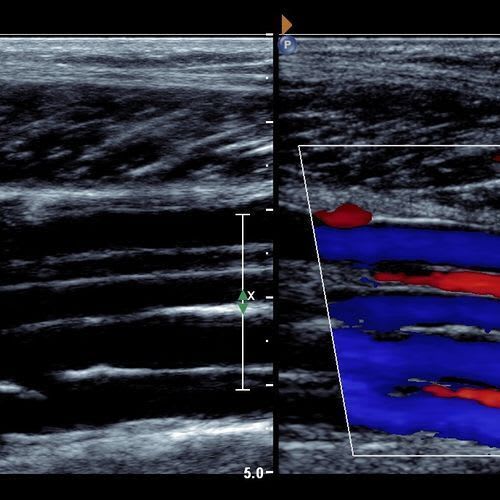

Vascular Screening

We recommend a vascular MOT for patient's over the age of 50. You check your teeth, your eyes, why not your veins & arteries too.